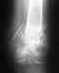

Дорого времени суток, уважаемые врачи! Болело в районе нижней трети левого бедра. В течении года, грешил на сустав коленный. Но боль усиливалась, и стала не выносимой. Сегодня сделали рентген, обнаружили патологию. Что это такое сказать не могут. Посмотрите снимок, пожалуйста. Что это можно быть??? Заранее спасибо!

• Кликните для загрузки файла IMG_20241218_203119.jpeg